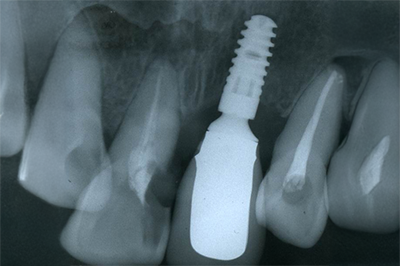

インプラント施術例

歯を削りたくない、入れ歯をどうしても入れたくないという時、インプラント治療を行っています。

レントゲン